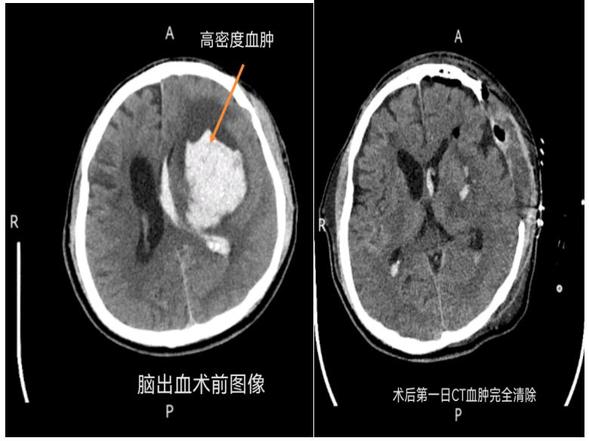

众所周知,脑出血发病急、进展快,严重时可在数分钟或数小时内危及生命。9月11日中午12时,一名从富裕县慕名而来的男性患者,因突发脑出血量约60ml破入脑室,且压迫脑干导致脑疝。脑疝的死亡率非常高,残疾率高,情况十分危急,需要立即进行开颅血肿清除手术。神经外一科张艳国主任和陈祥瑞副主任医师详细分析病情及制定手术方案,仅历时4个小时,顺利完成手术,术后患者状态良好。

脑出血术前及术后CT表现